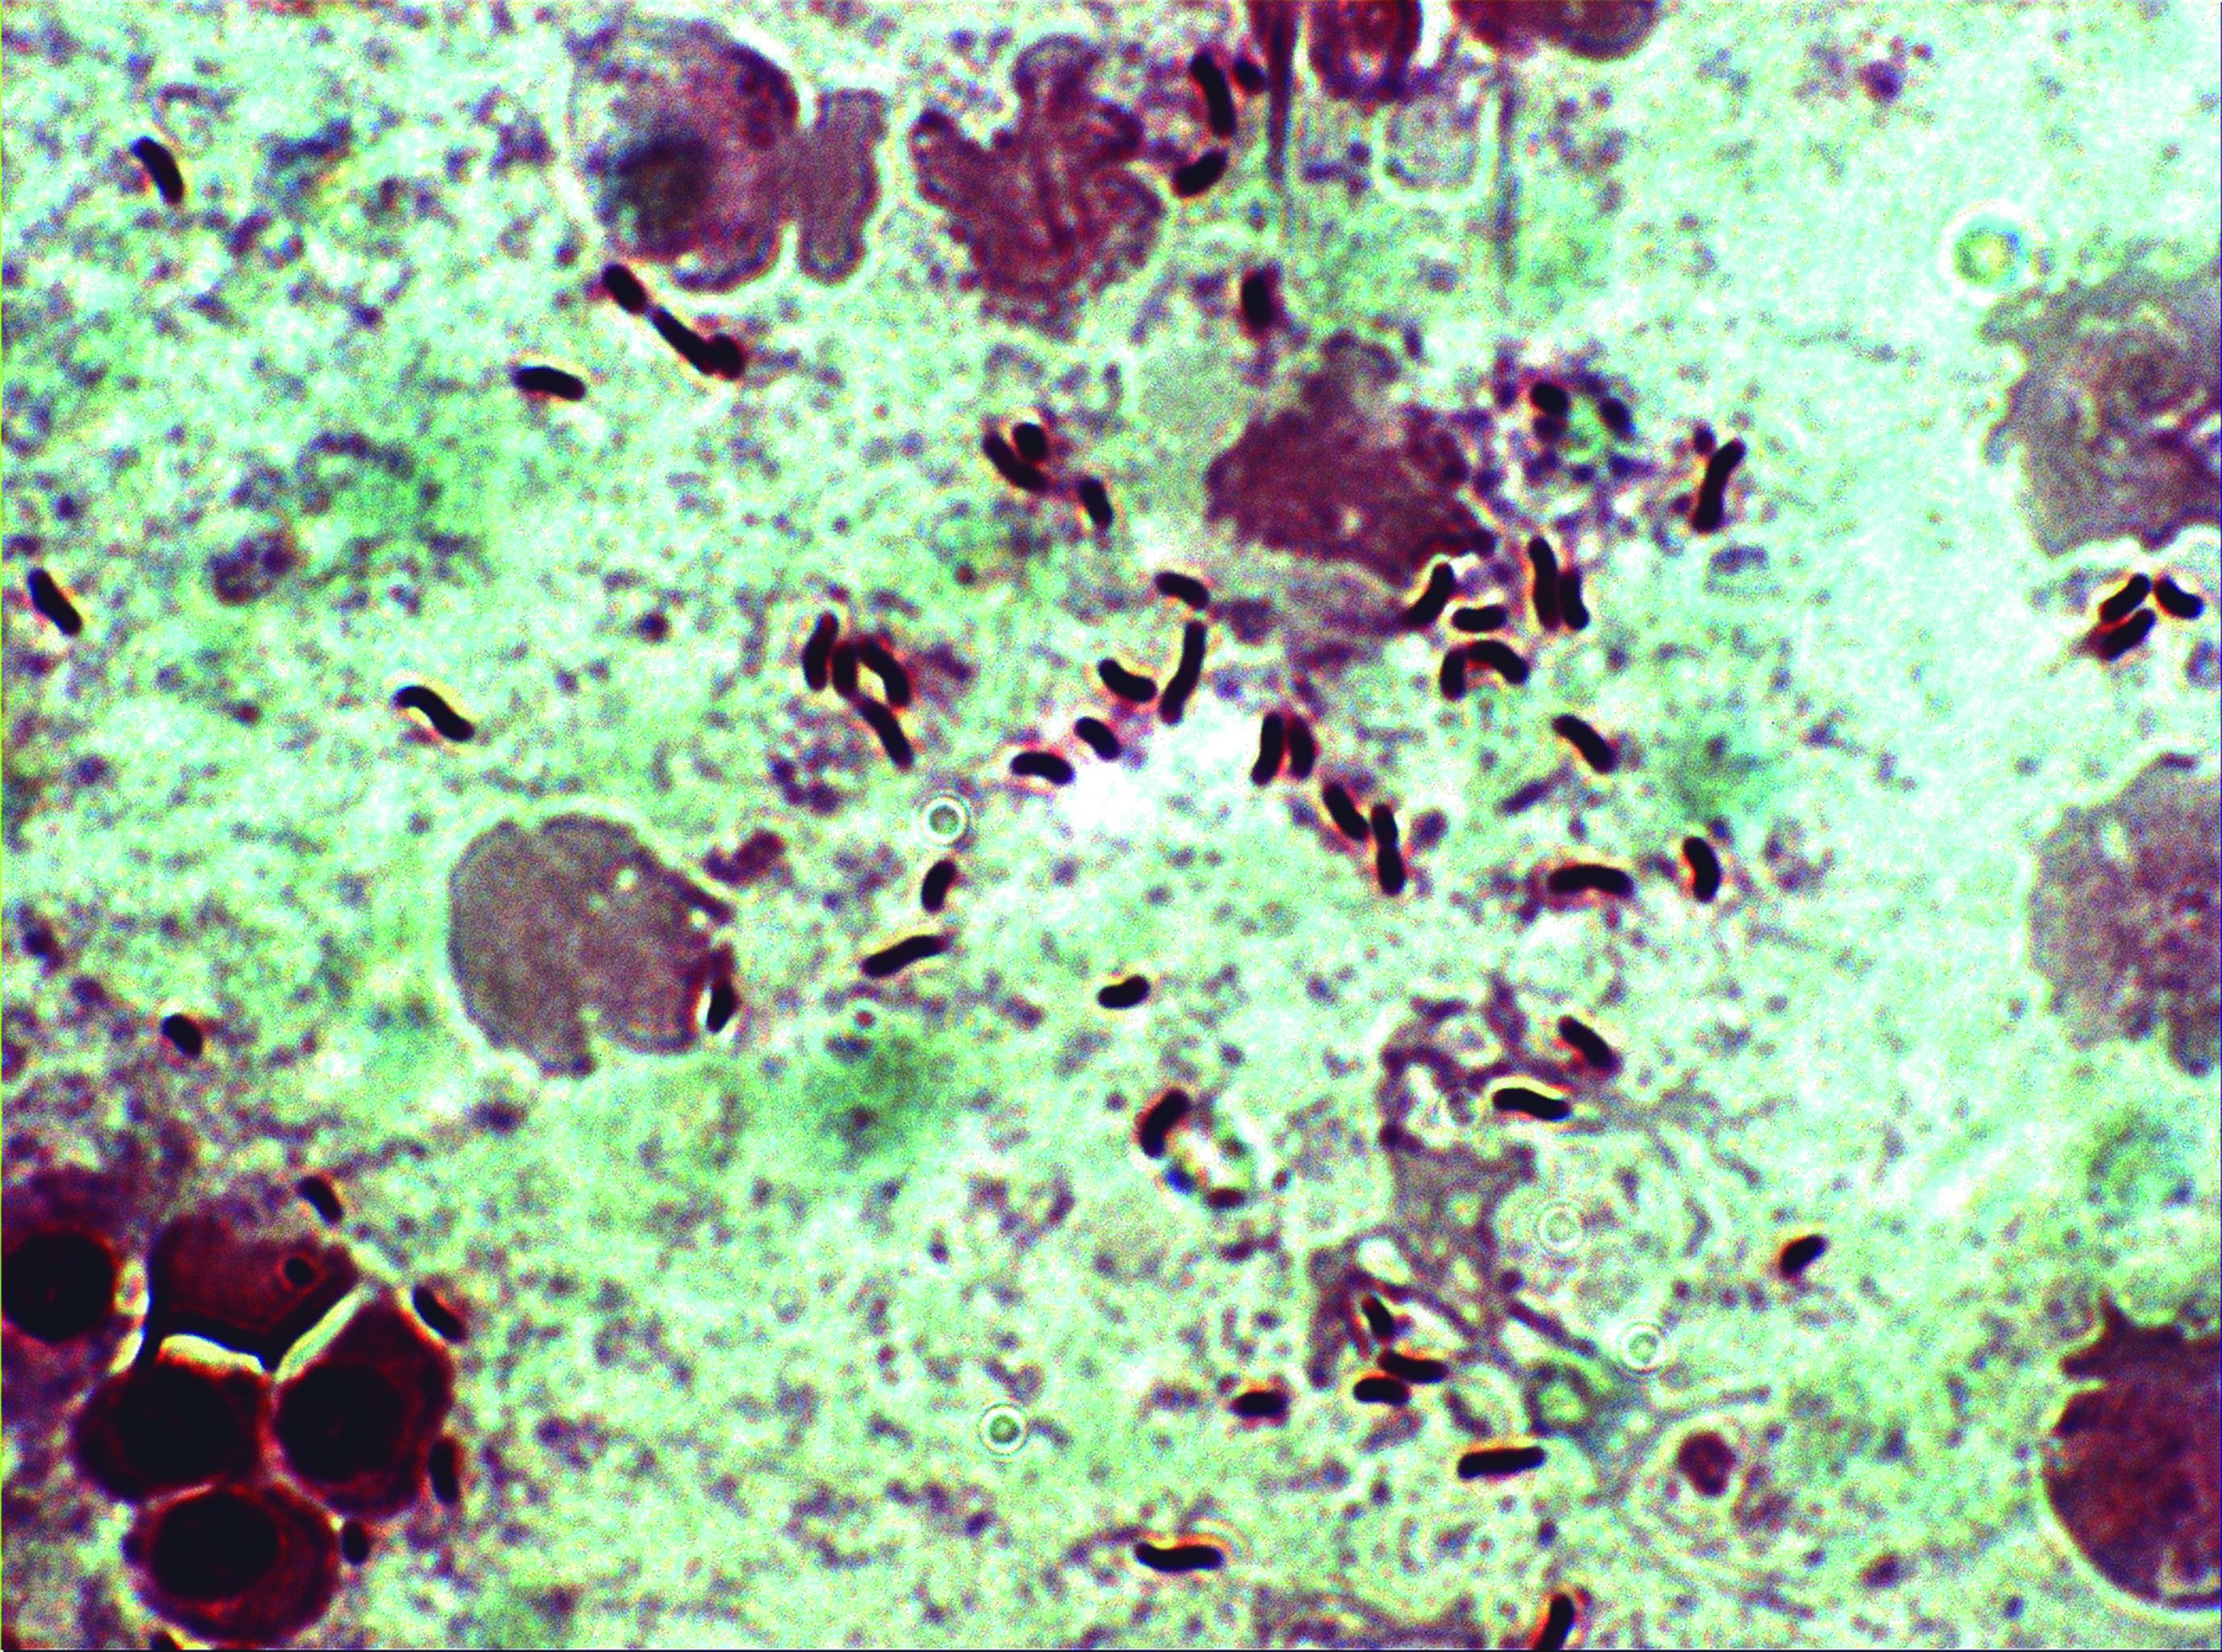

Mycobacteriosis

Agent: Mycobacterium spp. (Mycobacteriaceae, Acid-alcohol resistant Gram-positive rod-shaped small bacilli).

Symptoms: A chronic disease characterized by external hemorrhagic and ulcerative lesions, weight loss, and granulomas in internal organs. It occurs in warm water. Mycobacteria are zoonotic, so affected fish must be promptly removed. Some species of Mycobacterium are pigmented yellow or orange when cultured.

Control: Treatment is challenging, poor response to antibiotics.